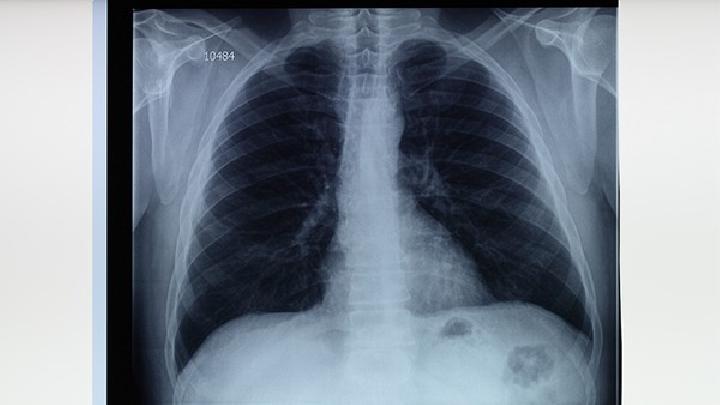

小细胞肺癌症状表现是什么?对于小细胞肺癌症很多人都不知道是什么疾病,但是说到癌症很人可能都会觉得非常的害怕和恐怖,总是担心不知道是什么样的症状,那么,下面我们一起来了解下小细胞肺癌症状表现是什么吧!